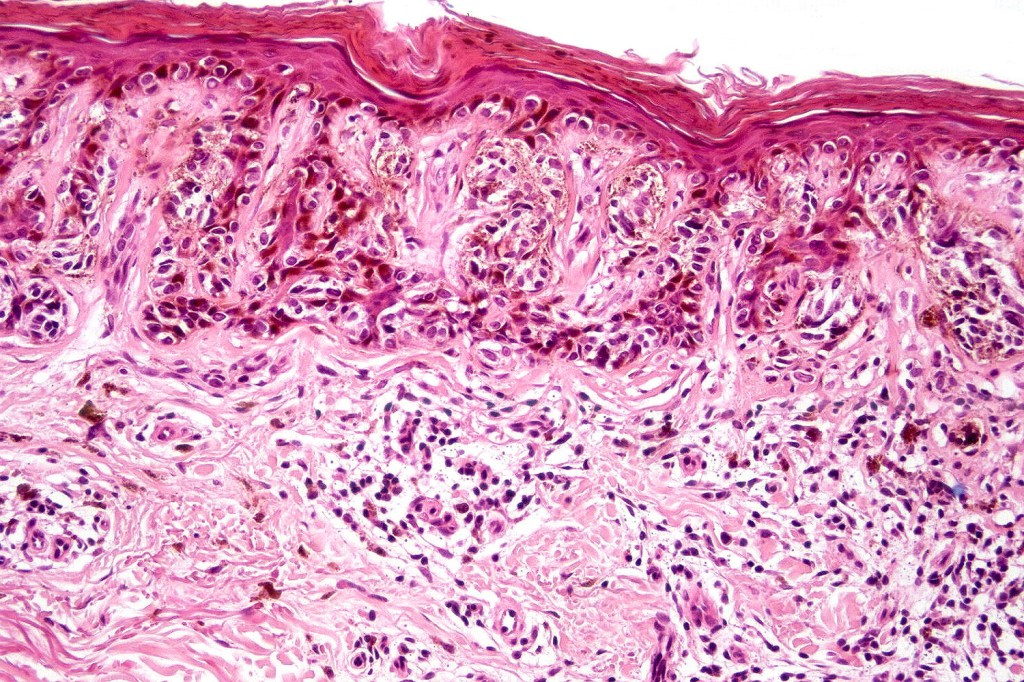

•Architectural disorder- lentiginous and nested, nests abnormally located (at the sides of the rete ridges & overlying the dermal papillae in addition to the tips of the rete ridges rather than solely occupying the tips of the rete ridges as is seen in banal nevi), horizontal orientation & bridging between junctional nests (this should not be confused with bridging between adjacent rete ridge squamous epithelium)

•Abnormal fine pigmentation (dusty)

•Host response- eosinophilic & lamellar fibroplasia, increased vascularity, lymphocytic infiltration & pigment incontinence